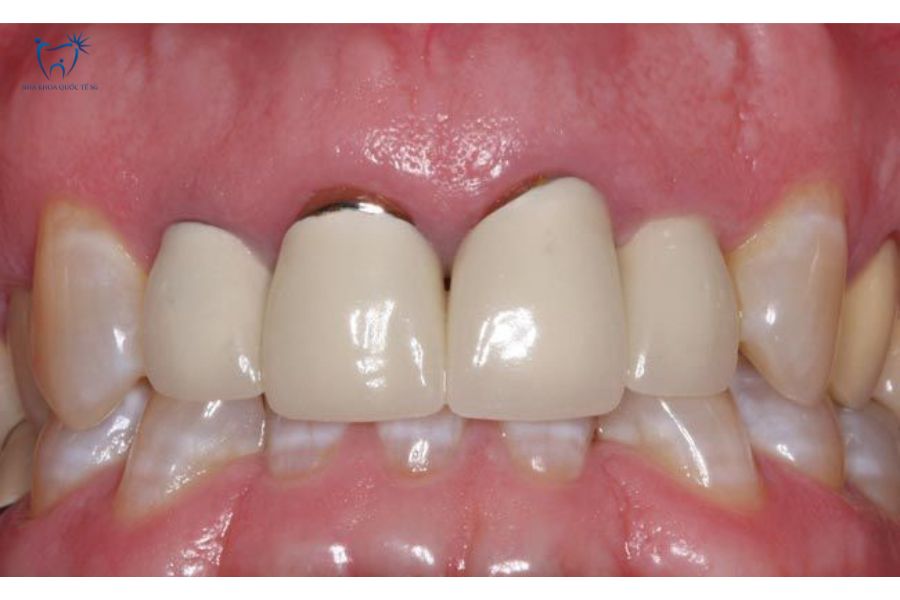

Hình ảnh thực tế cầu răng sứ bị hở

Cầu răng sứ bị hở là tình trạng xuất hiện khe hở giữa mão sứ và nướu hoặc răng trụ, gây đau nhức, ảnh hưởng thẩm mỹ và tăng nguy cơ nhiễm trùng.

Xuất hiện vệt đen mờ quanh chân răng sứ

Cầu răng sứ bị đen viền nướu

Dấu hiệu này đặc biệt phổ biến ở những người sử dụng cầu răng sứ kim loại. Khi cầu răng sứ kim loại không ôm khít với viền nướu, phần kim loại bên trong sẽ bị oxy hóa do tiếp xúc với môi trường ẩm ướt trong miệng, gây xỉn màu tại viền nướu.